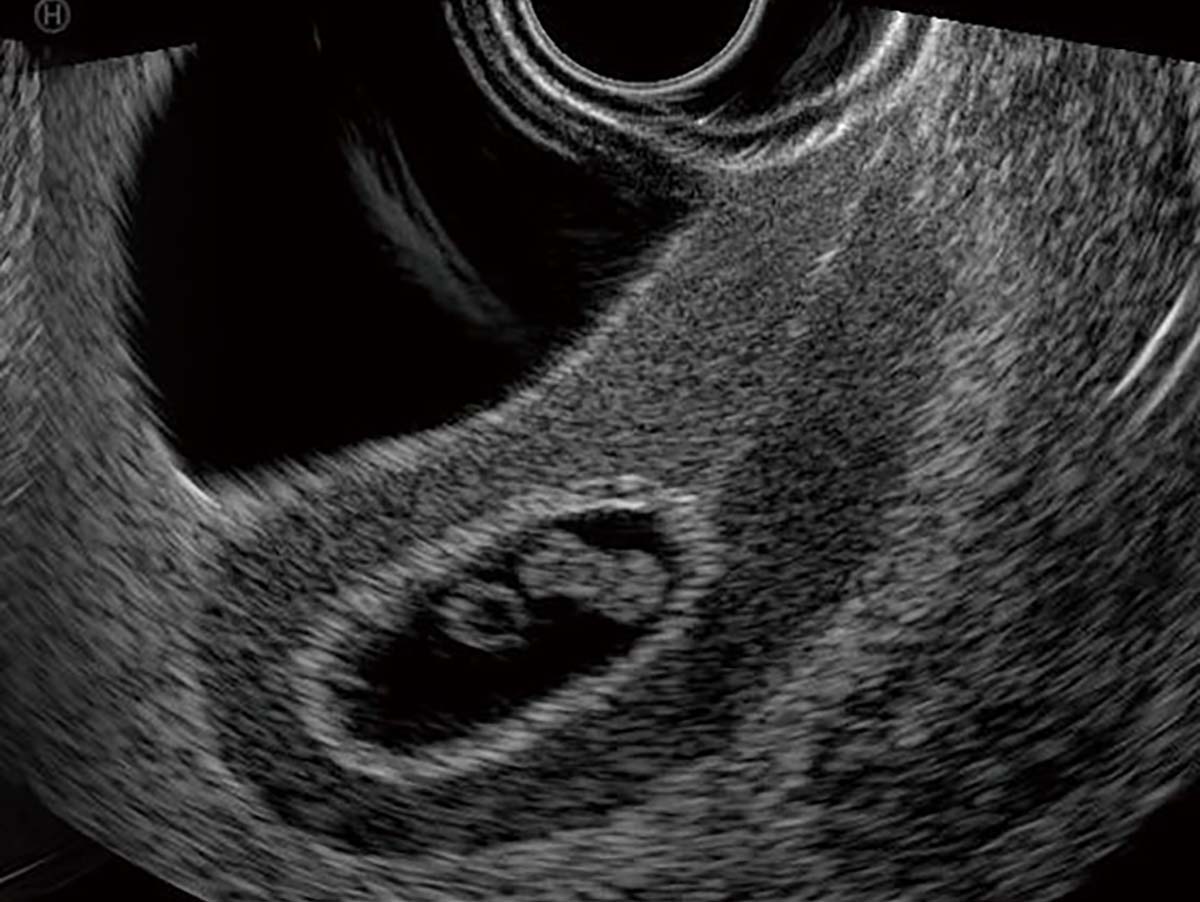

- Identification of normal and abnormal ultrasound appearances of the uterus, adnexa, and pelvic cavity in early pregnancy

- Introduction to transvaginal ultrasound: indications, technique, and interpretation